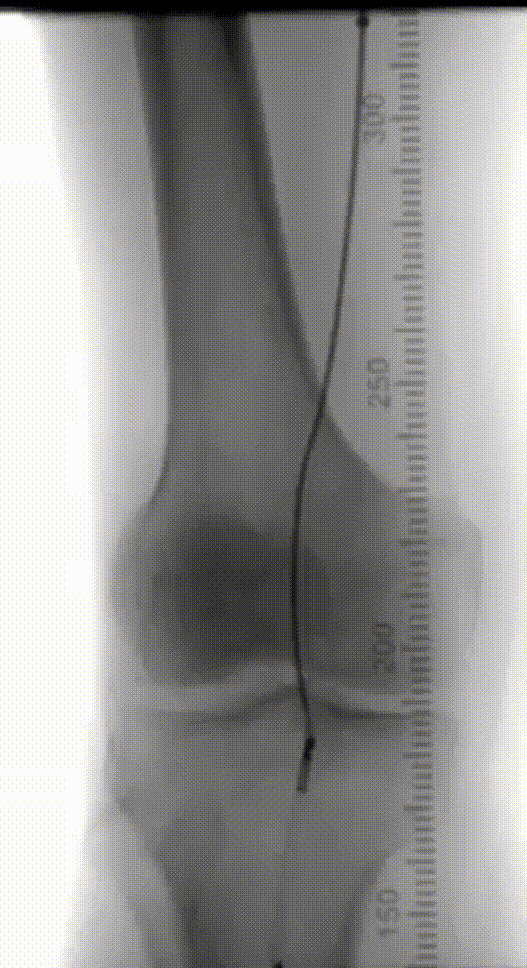

辅助检查:ABI(左0.72,右0.56),下肢动脉彩超显示双下肢动脉硬化伴多发斑块,右侧股浅动脉上段闭塞,双侧胫前动脉中下段接近闭塞。CTA提示:腹主动脉粥样硬化,右侧股动脉、双侧胫前动脉中重度狭窄、闭塞,左侧股动脉、双侧腓动脉、胫后动脉轻度狭窄,左侧髂内动脉局限性闭塞。

术前CTA

术前造影